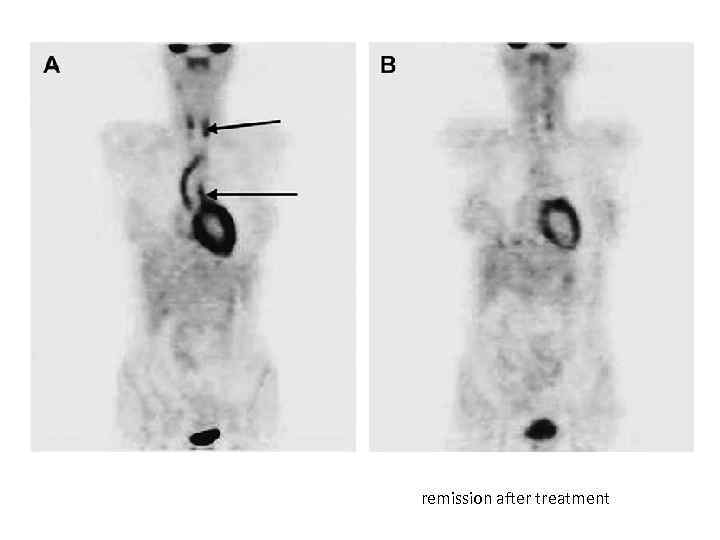

remission after treatment

Figure 7. Combination of 18 F-FDG PET and CTA for assessment of Takayasu arteritis. Heather L. Gornik, and Mark A. Creager Circulation. 2008; 117: 3039 -3051 Copyright © American Heart Association, Inc. All rights reserved.